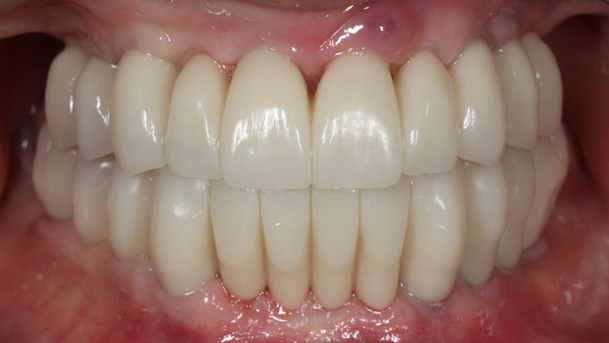

- Courtesy of Dr. Jong Cheol Kim, Korea

Dr. Jong Cheol Kim, edentulous, digital full-mouth prosthetics, digital guided surgery, guided surgery,R2 Studio, R2GATE Digital Oral Design, R2GATE DOD,flapless, AnyRidge, R2GATE, R2GATE full surgical Kit

AnyRidge implant system, R2GATE Guide, R2GATE surgical kit, R2GATE DOD, R2 Studio